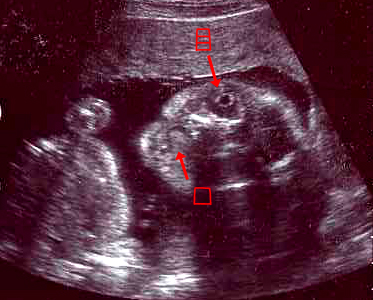

逆子が治ってました^^

28W1D

★頭の大きさ(横幅)7.42センチ

★体重 1195グラム

1週間ですごい成長!

ここから出産までは、2週間に300グラムのペースでどんどん大きくなっていく予定。

それにしても、逆子にならないでホッとしました。

いい子だな~と思ったら、エコーの表情も余計に可愛くみえます。。

前回はヘンな格好していたけど、

今回は両膝を折り曲げた、あのよく見かける胎児のポーズをとっていました。